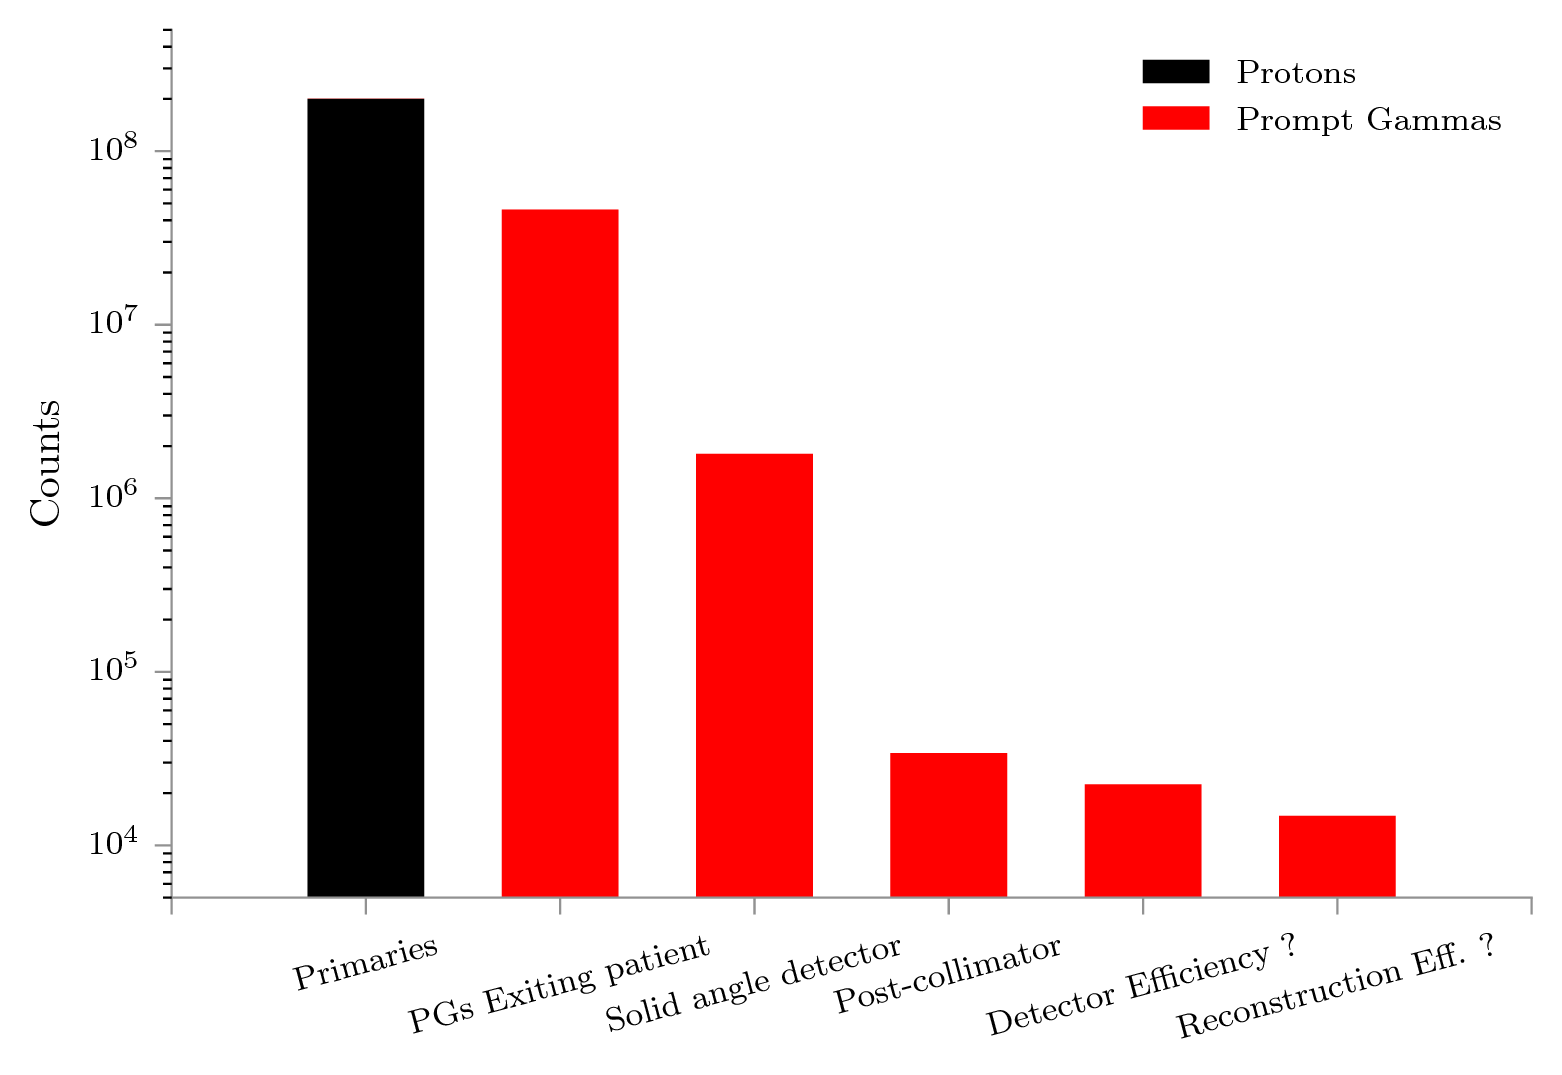

Imaging paradigms such as PG detection are validated against experiments, and often also with Monte Carlo (MC) simulations (Golnik et al., 2014; Gueth et al., 2013; Janssen et al., 2014; Moteabbed et al., 2011; Robert et al., 2013). Conventional MC methods propagate particles according to a set of physical processes through materials. The tracking of a particle is broken up into steps, where at each point, a weighted list of all possible next steps is built and one option is selected by a random number. For rarely occurring processes, convergence to the model of the truth to within acceptable statistical error can be slow. PG emission in particle therapy, when viewed on a voxel-by-voxel basis, is also a rare and slowly converging process (Gueth et al., 2013; Pinto et al., 2015; Sterpin et al., 2015). This has important implications: firstly for detector designers, secondly for those who simulate, and thirdly for those interested in comparing the two online in, say, clinical conditions. In the first case, detectors are optimized to minimize signal loss (see fig. 1) and advanced reconstruction can be employed to maximize the use of information in the signal. Gueth et al. (2013) has demonstrated a method that works around the low PG yield by using machine learning to correlate predefined patient translations (setup errors) to PG output signals, which reduces the time to produce an estimated translation based on the detected PGs. Since convergence to the model of the truth requires long simulation runtimes, we may compensate with variance reduction methods or cutoffs in the time, space, or spectral domains (e.g. fixed runtime, larger voxel size, larger spectral bins). One such variance reduction method is MC splitting, where the moment a rare process occurs not one, but multiple possible futures for that process are computed. The weighted total of these futures are then stored, and so the convergence accelerated.